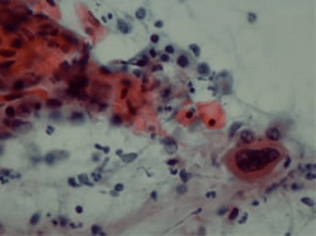

組織診と細胞診

肺がんの最終的な判定を行う方法は組織診と細胞診の2種類があります。組織診は検査、あるいは手術でとってきた組織の切れ端をホルマリンで固定し、薄くきった後H-E染色(ヘマトキシリンとエオシンという色素を使うのでこの名前がついています。)して顕微鏡で見ます。細胞の大きさ、形、並び方などを総合的に判定します。別の特殊な染色を使って特定の性質を判断することもあります。

細胞診は、はがれてきた(喀痰細胞診)あるいは剥がしてきた(擦過細胞診)もしくは針を刺して吸引してきた(吸引細胞診)細胞をアルコール固定し、パパニコロー染色という方法で染めて顕微鏡で見ます。細胞の並び方を判断することは困難で、主として細胞の大きさ、形から判断します。

痰に混じったがん細胞を見つけ出す:喀痰細胞診

喀痰細胞診

喀痰とは吐き出した痰のことです。肺の組織から剥がれ落ちて痰に混じったがん細胞を検出する検査です。人間の目で喀痰中のがん細胞の有無をチェックします。検査は専門のスクリーナーという技師が行います。

検査の手順は、できるだけ早朝の喀痰を容器に入れ、乾かないようにして提出するだけです。患者さんにとって苦痛のない簡単な検査ですが、肺がんがあれば必ず痰にがん細胞が混じっているとは限らず、喀痰細胞診の結果が正常であったからといって肺がんがないという証拠にはなりません。

そのため喀痰細胞診は何回か繰り返し行うことで、がんがあった場合の診断精度が高まるとされており、通常3回は行って喀痰中のがん細胞の有無を調べることになっています。

細胞診検査では、検体(この場合痰のことです)をスライドグラスの上で伸ばしてアルコールで固定し、染色して顕微鏡で細胞を観察します。がん細胞があると疑われる場合には、スクリーナーとは別に医師が確認するという手順を踏みますので、結果が出るまでは数日かかります。